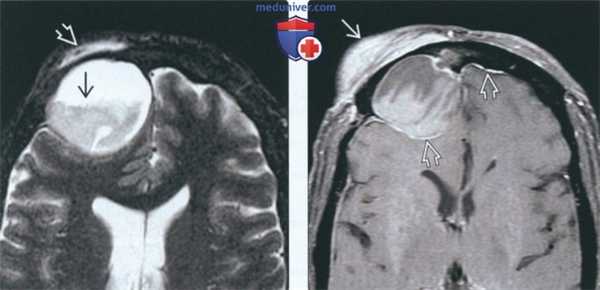

(Слева) На аксиальной МРТ (Т2 ВИ FS) определяется большое мукоцеле правой лобной пазухи с уровнем «жидкость-жидкость» и компонентами с различной интенсивноаью сигнала. Мукоцеле распрсктраняется в поверхностные мягкие ткани, приводя к отеку.

(Справа) На аксиальной MPT (Т1 ВИ FS) у этого же пациента определяется отек и контрааное усиление поверхностных мягких тканей над разорвавшимся мукоцеле. Контрастирование твердой мозговой оболочки в передней черепной ямке сопоставимо с ранними воспалительными изменениями.